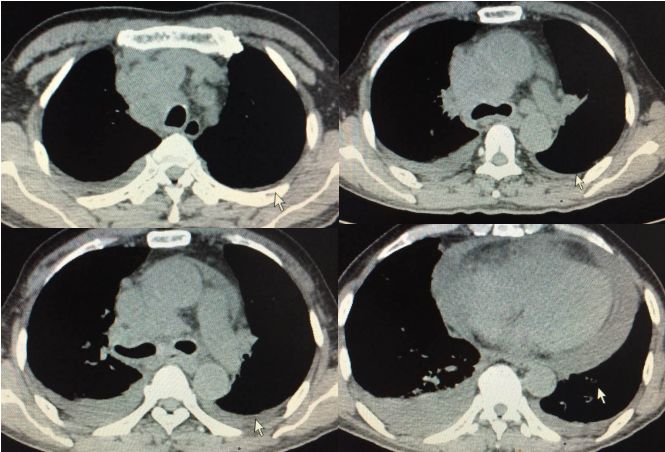

老王入院后,给予常规抗感染对症治疗,气喘进行性加重,短期内出现双侧大量胸腔积液,大量心包积液伴双下肢浮肿,继发呼吸衰竭、心功能衰竭。复查胸部CT示双侧胸腔积液和心包积液较前明显增多(图5)。

图5. 2016.1.7复查胸部CT提示胸腔积液快速进展